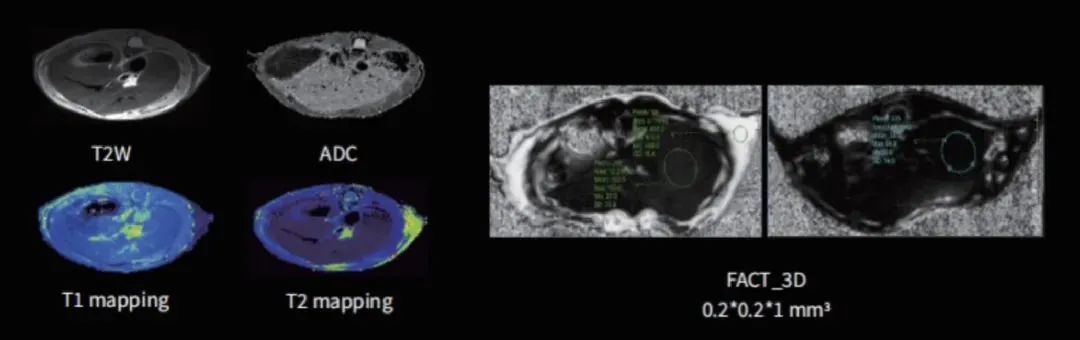

小动物腹部研究

利用其高分辨率和软组织对比度优势,核磁共振能够精确检测和分析小动物腹部器官的细微病变。可通过T2W、ADC、T1/T2 mapping、FACT_3D等技术成像(如图9),观察组织器官形态,评估组织微观结构,为疾病模型研究和药物测试提供重要数据。

图9 不同序列下腹部组织成像